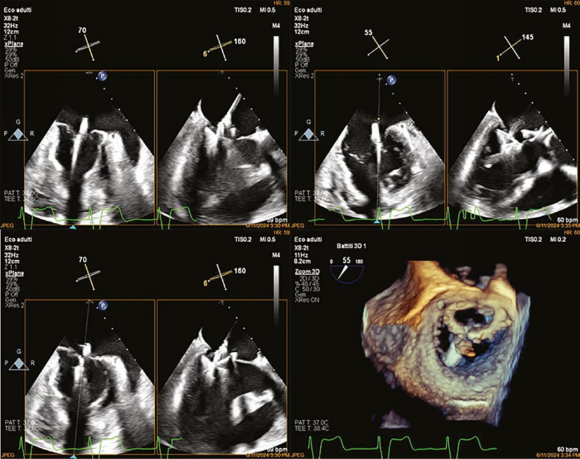

病例概述患者为84岁男性,无吸烟史,2012年诊断为轻中度二尖瓣反流和轻度三尖瓣反流。2014年因永久性心动过缓性房颤植入单腔起搏器(VVI模式)。2015年病情进展为重度混合性MR(退行性+功能性),超声心动图显示中心性反流束(面积>10 cm²,缩流径8 mm),左室射血分数(LVEF)降至0.39,遂行外科二尖瓣修复术,植入28 mm Sorin Memo 3D成形环。

2023年6月,患者因右腿血肿暂停抗凝治疗,CT发现髂总动脉穿透性溃疡及右髂内动脉瘤(直径4.5 cm),接受主动脉-双髂动脉覆膜支架治疗。同年7月随访超声提示左室收缩功能进一步下降,二尖瓣出现偏心性反流束,成形环部分脱位导致瓣膜功能障碍。至2024年5月,MR进展为重度(双偏心反流束),左室舒张末容积指数(76 mL/m²)、左房容积指数(76 mL/m²)增加,LVEF为43%。患者心功能恶化至NYHA III级,但因高龄、严重左室功能障碍、糖尿病、房颤等高危因素,传统外科手术风险极高(STS评分提示禁忌),最终决定采用PASCAL Ace系统行经皮修复。

手术过程

心脏团队综合评估认为,成形环脱位通常需外科二次手术(如瓣膜置换),但该患者解剖复杂(脱位环阻碍器械操作)、合并血管病变,且存在左室功能不全,手术风险不可接受。PASCAL系统虽无成形环脱位修复的长期数据,但其设计灵活性(如独立抓取瓣叶、可调节夹合宽度)为挑战性病例提供了可能。